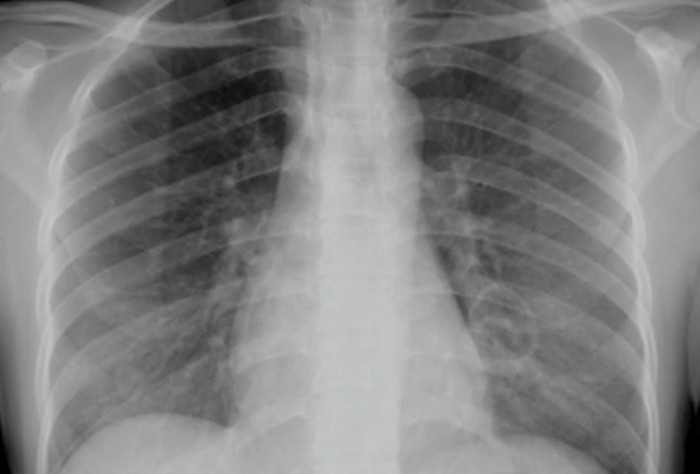

Hình ảnh XQ phổi người bệnh sau khi điều trị. (Ảnh: BVCC)

Sau 4 ngày điều trị, tổn thương phổi và tình trạng suy hô hấp nặng của bệnh nhân được cải thiện. Bệnh nhân cai máy thở thành công sau 7 ngày thông khí xâm lấn và phục hồi gần như hoàn toàn sau 14 ngày điều trị.